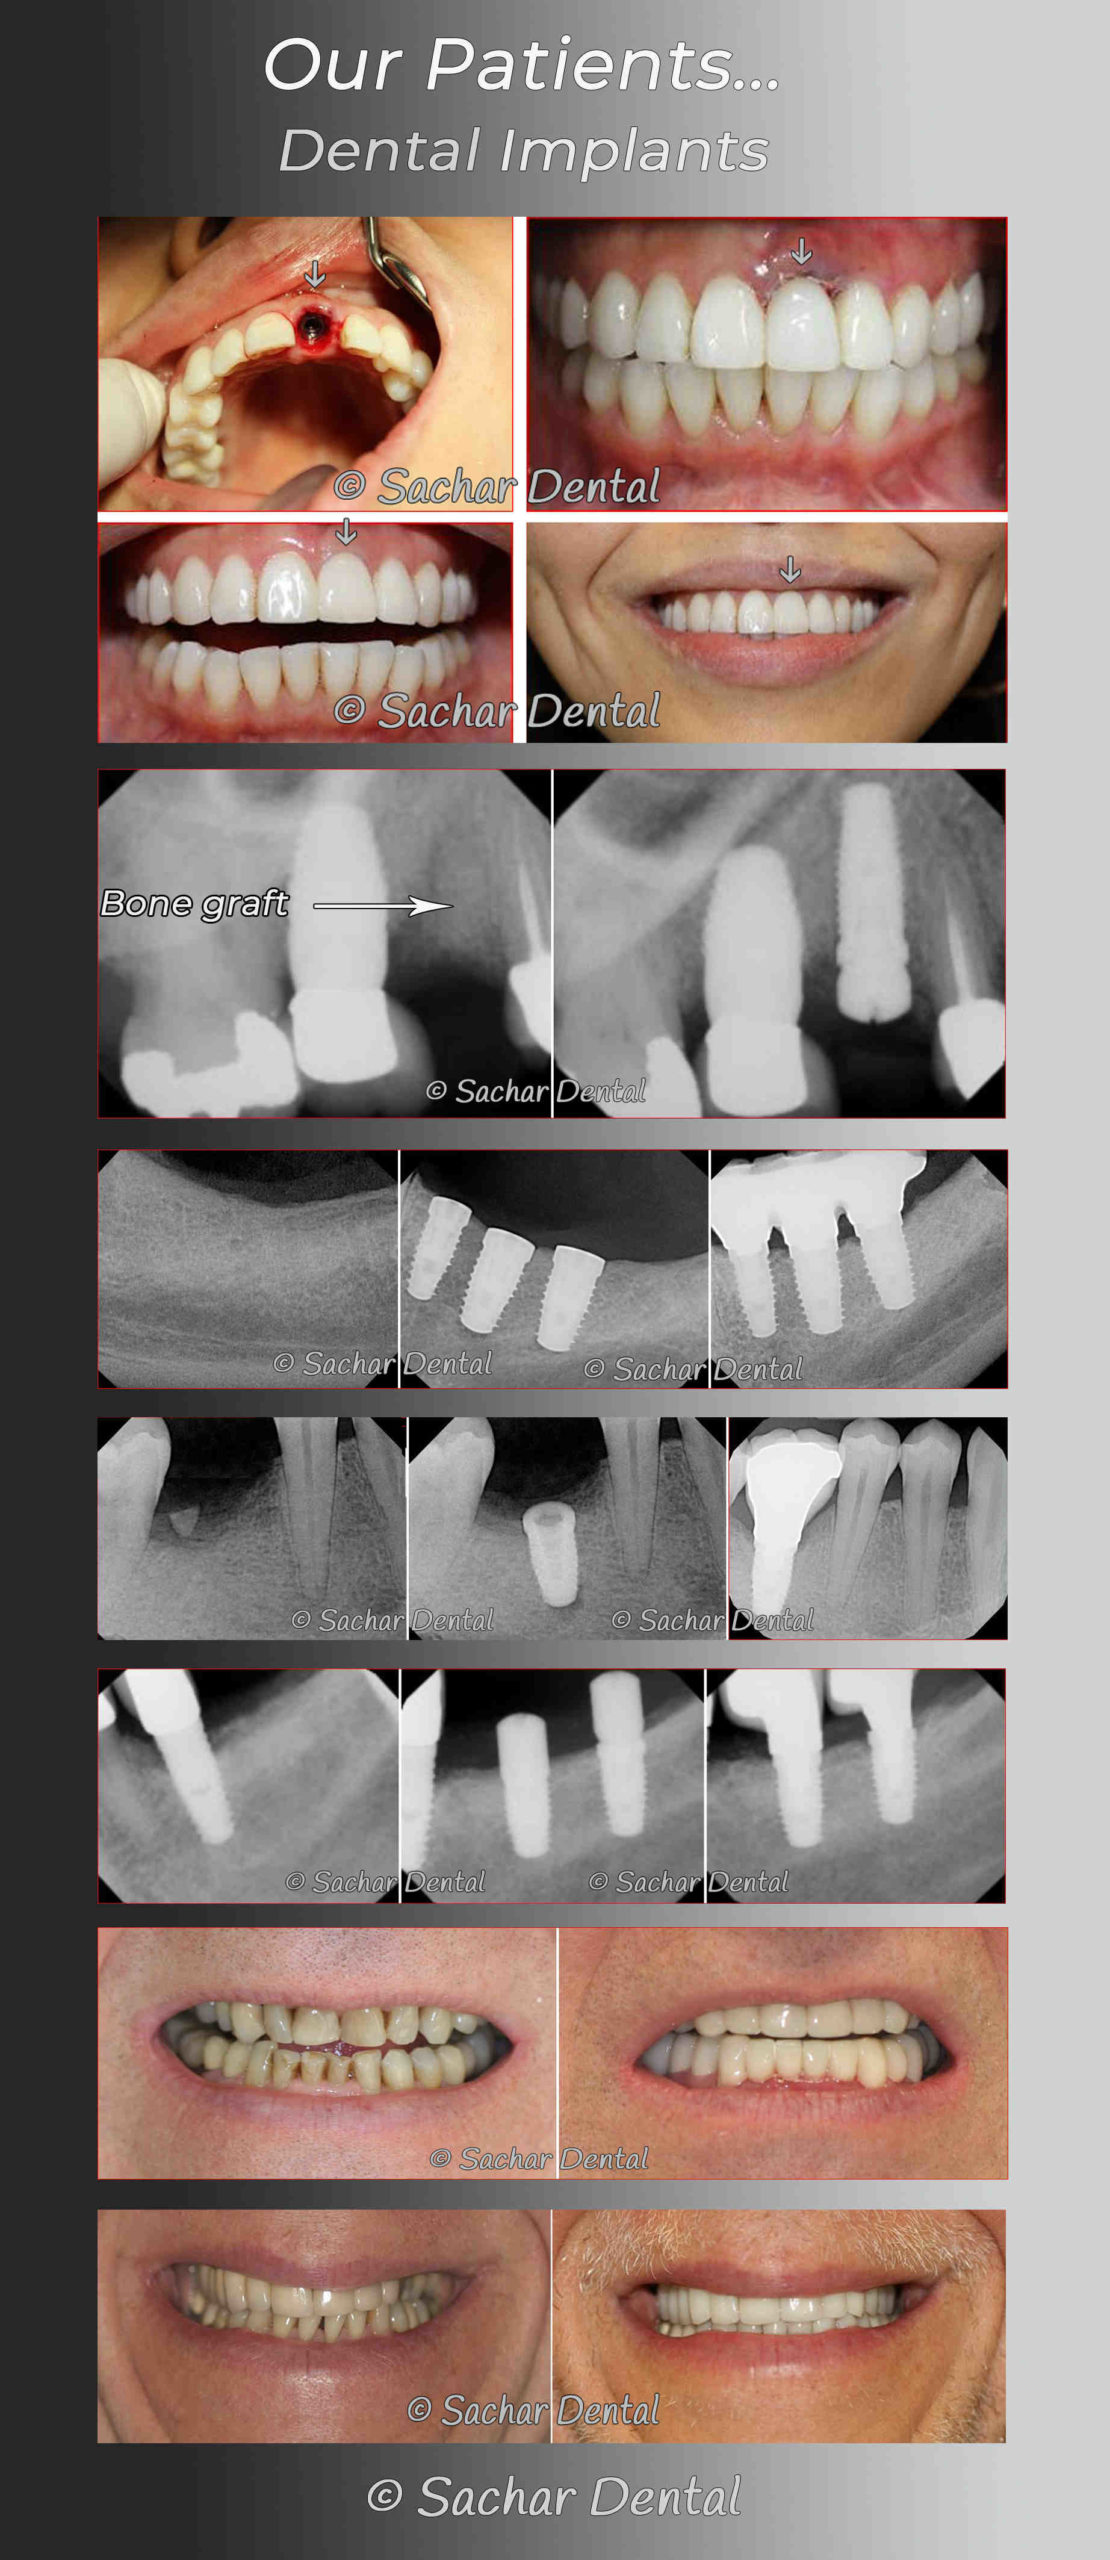

How do you fix a failed dental implant?

In severe cases, your dentist will usually need to perform a bone grafting procedure before replacing a failed implant. This may interest you : Dental Implants Abutments. Bone transplantation is a procedure in which new bone is grown.